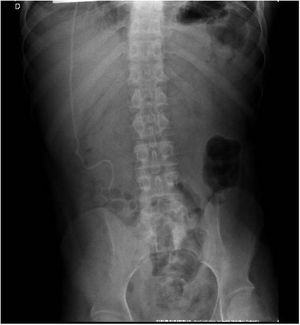

For 4 years, he had several arteriovenous fistulas and short and long-term vascular catheter implants resulting in central vein thrombosis and stenosis. The patient underwent bladder enlargement (Mitrofanoff) and external urinary diversion for subsequent kidney transplantation. The patient evolved with failure of vascular access for HD and a Tenckhoff catheter was inserted (Fig. 2) and PD started, a procedure did not have infectious/neurological complications for 6 months.